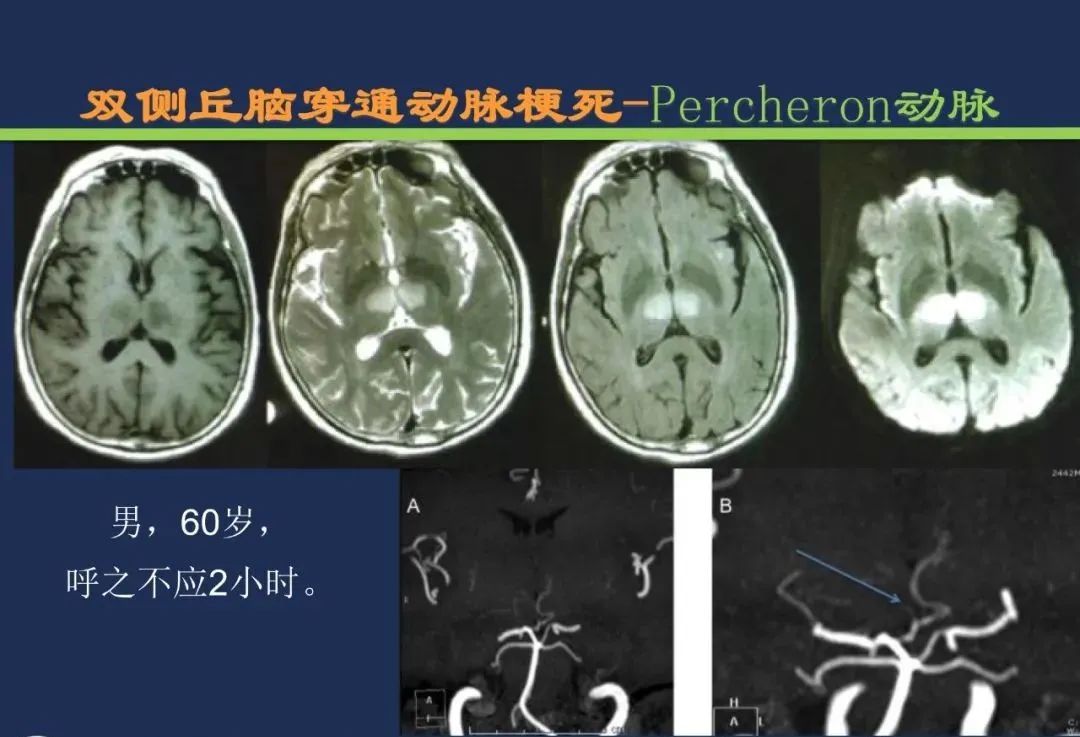

椎基底动脉梗死大脑后动脉丘脑穿通动脉-Percheron动脉